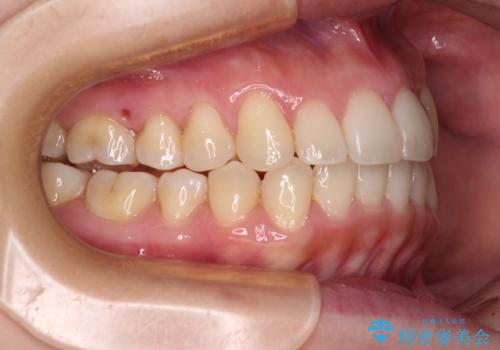

- 八重歯と前歯のデコボコを気にして来院された患者様です。

八重歯の他に、上顎歯列を狭窄しているという問題点がありました。

また、八重歯により上顎奥歯が前方に位置しており、咬み合わせの改善も必要な状況でした。

インビザラインによる矯正治療を希望されたため、上顎歯列の側方拡大奥歯の遠心移動のための補助装置を併用し、その後はインビザラインにて行うこととしました。